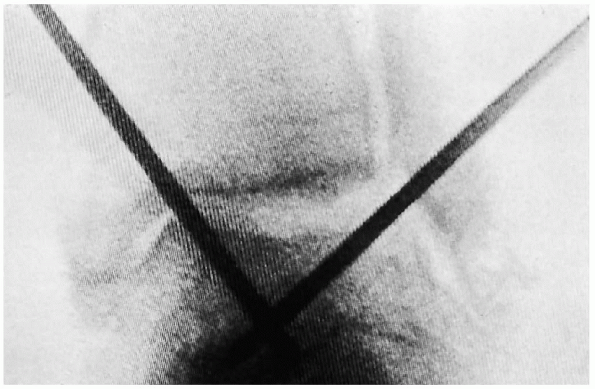

Depending on the location of the lesion on the talar done, drilling can

be done with 0.062-inch Kirschner wires (K-wires) through the medial

malleolus (i.e., transmalleolar approach) or through the anteromedial

portal. If the fragment is viable and is not too posterior, it can be

fixated with absorbable pins or small, cannulated screws. When

absorbable pins are used, stable fixation is achieved by using two or

three pins. Stabilization of the lesion before

drilling may be obtained through an accessory anteromedial portal with

a small probe or a smooth K-wire. If the fragment is too posterior, fixation may be

![]() |

FIGURE 31-22. The lesion was drilled before fixation with a biodegradable pin.